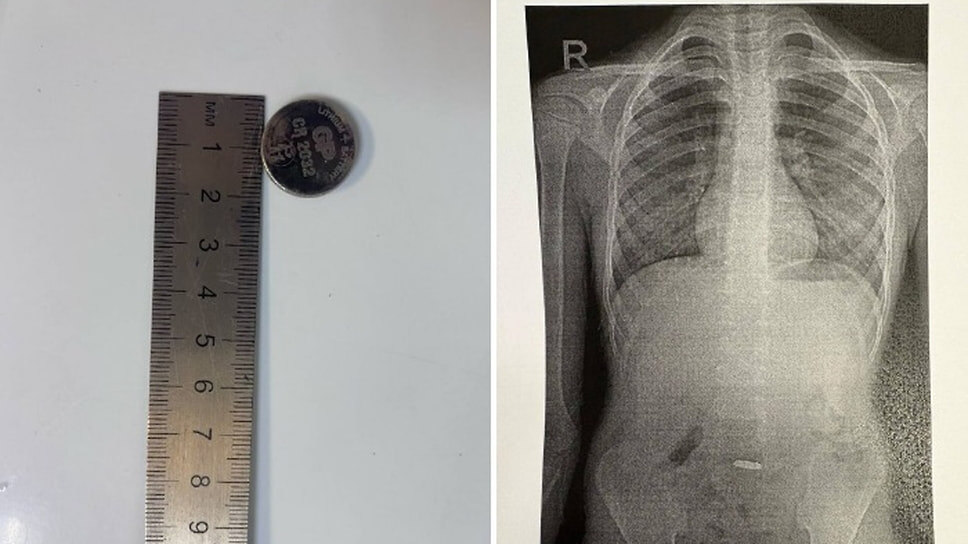

Врачи городской больницы Новороссийска спасли 7-летнего ребенка, проглотившего литиевую батарейку. Медикам удалось извлечь ее из желудка пациента при помочи специального «сачка», сообщили в Telegram-канале ГБУЗ ГБ №1 Новороссийска. «Ребенок поступил в больницу с жалобами на тошноту и рвоту. Рентген-диагностика, проведенная заведующим отделением лучевой диагностики Гором Петросяном, выявила причину — в желудке малыша находилась круглая батарейка. Батарейки, особенно литиевые, при контакте со слизистыми оболочками вызывают химические ожоги, некроз тканей и могут привести к перфорации органов уже через 2–4 часа. Извлечь их нужно как можно быстрее!»— прокомментировали врачи. Специалисты эндоскопического отделения горбольницы под руководством Давида Шагиняна смогли извлечь батарейку из желудка ребенка с помощью специального сетчатого инструмента — «корзинки-сачка». Гладкая поверхность батарейки не позволяла зацепить ее обычными щипцами, резкие движения могли повредить пищевод или сломать ин

Фото: Telegram-канал ГБУЗ ГБ №1 Новороссийска